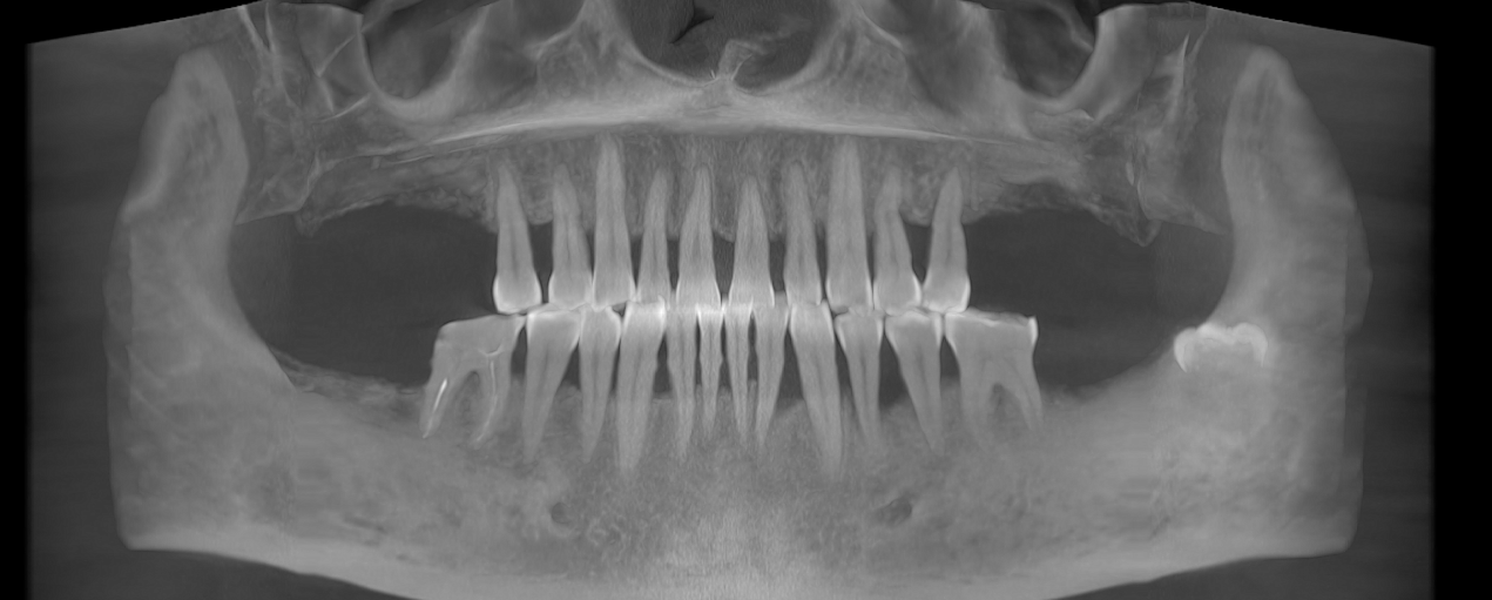

- Consultație, radiografie și plan de tratament personalizat